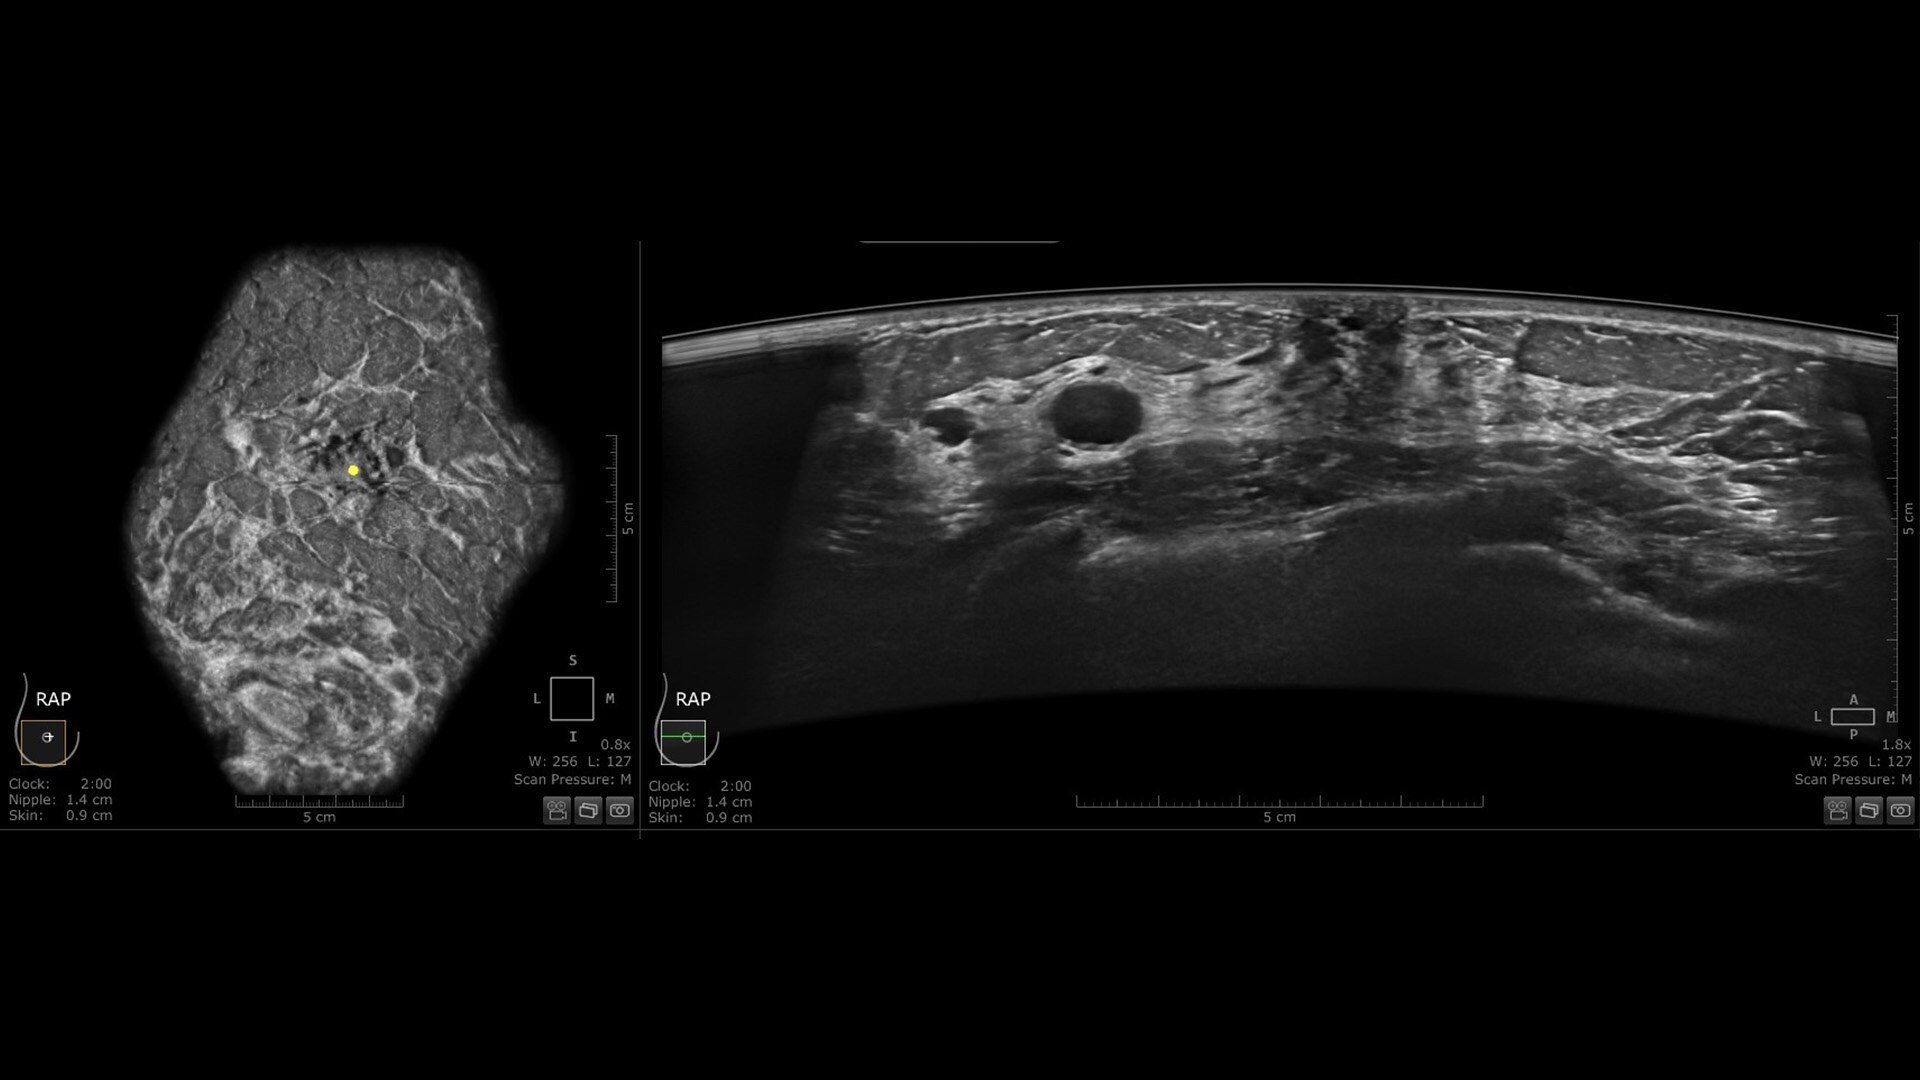

The Invenia ABUS Premium is designed for high patient throughput and extraordinary image quality to provide a great level of confidence. With its innovative design, it’s easy to use, reproducible, user-independent, standardized and allows reading anywhere.

The novel Reverse Curve™ transducer is designed for enhanced performance

Its gentle 15.3 cm shape follows the breast's natural contour, enhancing patient comfort* and ensuring full contact for comprehensive coverage. The improved image quality* increases diagnostic confidence for reading ABUS exams.

Excellent image quality and 40% faster scan speed

• cSound Imageformer, software-based processing, produces exquisite, reproducible images by leveraging automatic focus at every pixel.

• Fast Scan increases scan speed by 40%*, fostering improved efficiency and patient throughput.

• Decrease benign biopsies by up to 55% with Koios DS™ Breast